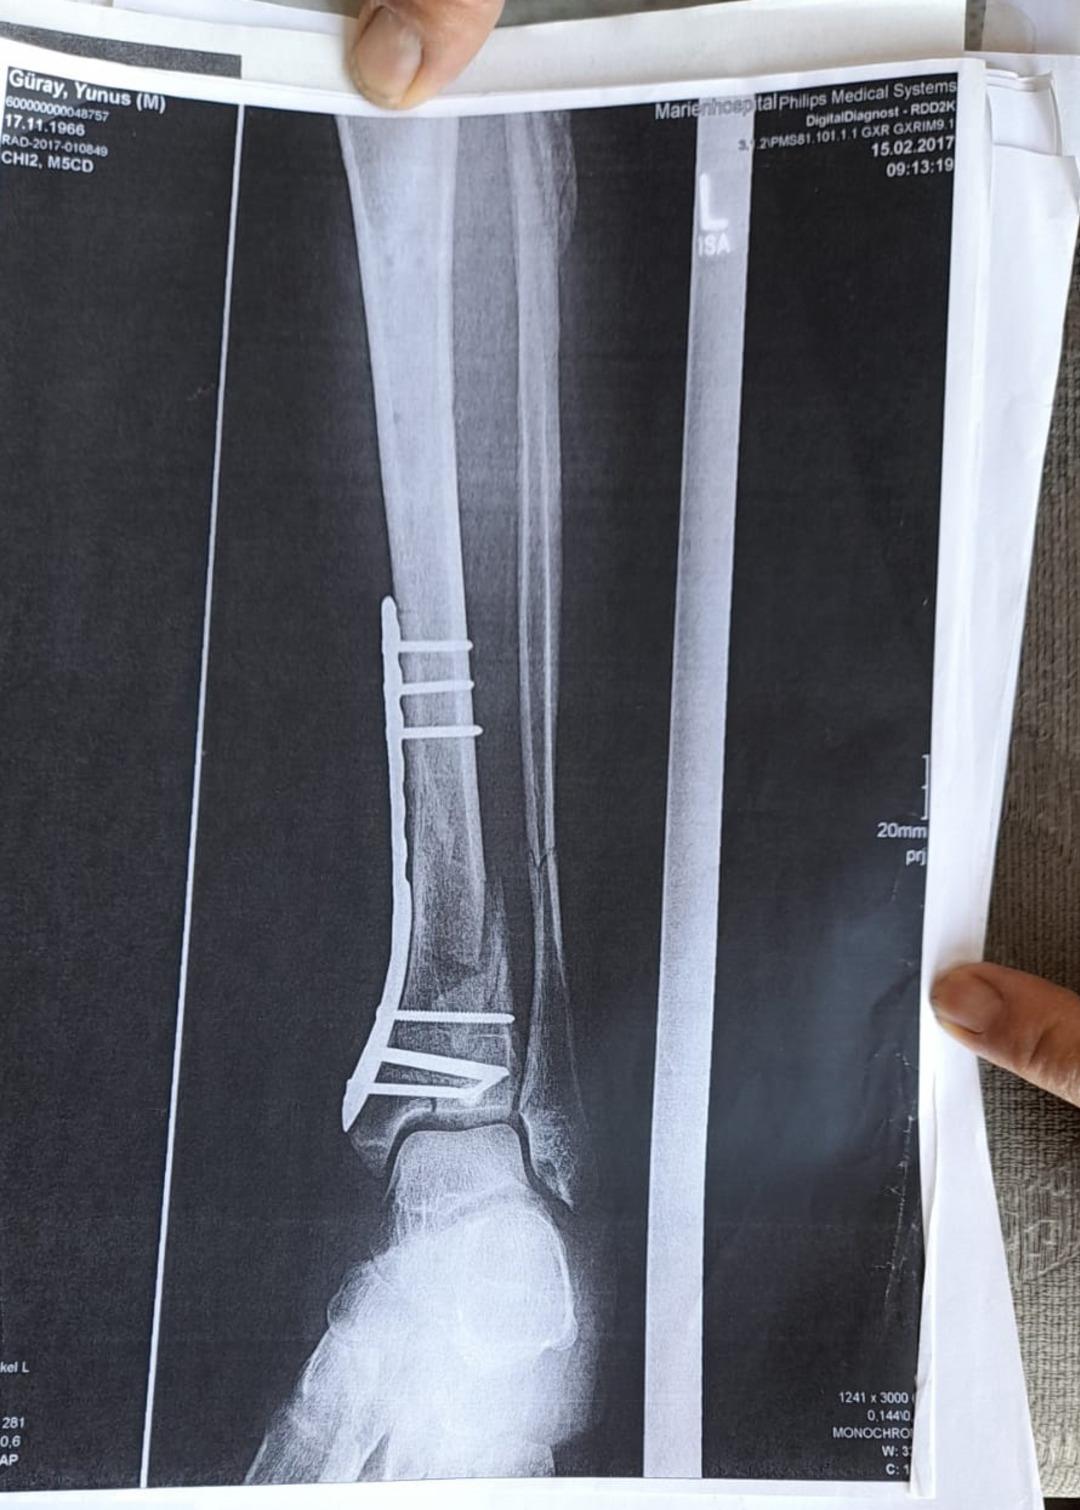

Olay yeriyle ilgili fotoğraf ve görüntüleri mahkemeye sunduklarını kaydeden Güray, "Ömrümü yediler, demir var ayağımda, sakat bıraktılar. Ayağı keseceklerdi neredeyse. Şu an kalıcı sakatlık var. 1 sene kendime gelemedim, 2 haftada bir ameliyata giriyordum. Almanya'da 3 ay hastanede kaldım ve ayağımda yüzde 3'lük engel oluştu" dedi.

Tazminat miktarını düşük bulan Yunus Güray, şunları söyledi: "Benim uçak masrafım sadece 22 bin avro tuttu. 9 yıl oldu, bir tane çukur değildi. Adamlar kazmış, kazmış, bırakmış. Tam merkezde bu olay, hani ormanda bir yerde olur, 'Tamam benim de hatam var. Gittim de düştüm' derim. Ama şehrin merkezinde, etrafı çevrili değildi. Yemyeşil alan, gece vaktiydi. Ben mahkemeye verdim, o çukurları 3 ay sonra kapattılar. 6- 7 yerde kazılmış çukurlar vardı. Bir tane değildi. Ayağımda hala demir var. Adil bir karar olmadı."